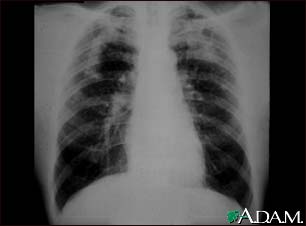

Coal workers pneumoconiosis, complicated

This picture shows complicated coal workers pneumoconiosis. There are diffuse, small, light areas (3 to 5 mm) in all areas on both sides of the lungs. There are large light areas which run together with poorly defined borders in the upper areas on both sides of the lungs. Diseases which may explain these X-ray findings include complicated coal workers pneumoconiosis (CWP), silico-tuberculosis, disseminated tuberculosis, metastatic lung cancer, and other diffuse infiltrative pulmonary diseases.